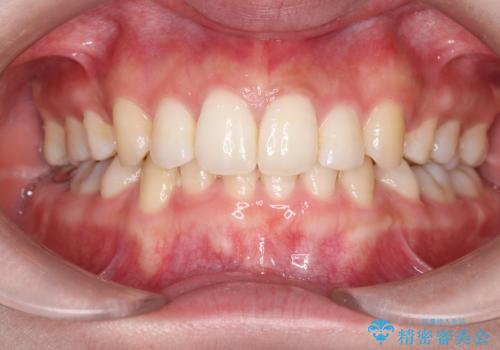

今回の治療では、重度の叢生を改善するため、まず計画通り上下左右4本の小臼歯を抜歯し、歯を並べるための十分なスペースを確保しました。装置には透明で取り外し可能なインビザラインを使用。抜歯によってできたスペースを最大限に活用し、マウスピースを定期的に交換しながら、デコボコを解消しつつ、前歯を効果的に後退させました。

治療の結果、長年の悩みであった重度の歯のがたつきが解消され、口元の突出感も改善。機能的にも安定し、審美的にも美しい、理想的な歯並びを獲得していただけました。